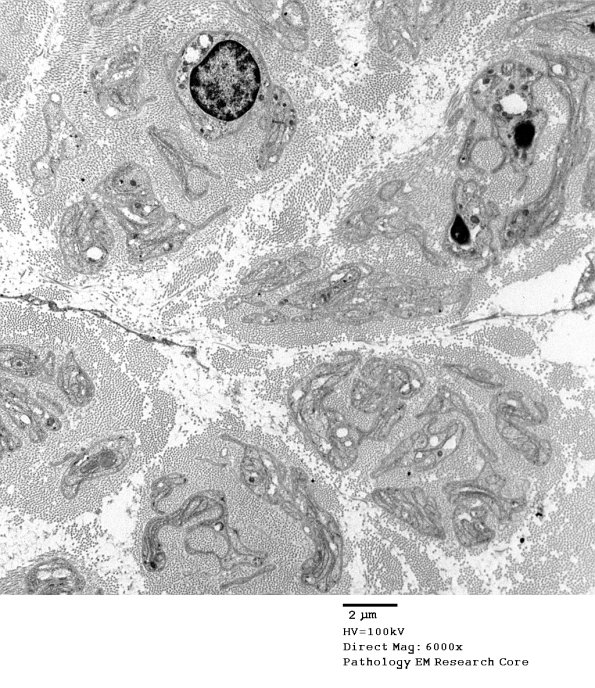

Ultrastructural examination was performed to further explore the nature of the onion-bulb formation in this case, i.e., is this an example of true vs. pseudo-onion bulbs? ---- 1C1,2 These images show the pathologic substrate in this case which is nearly complete loss of axons with numerous bands of Büngner. (electron micrographs)